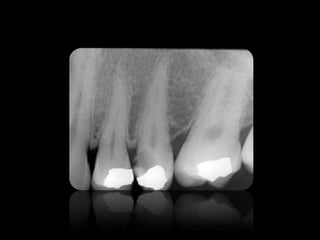

CARIES

10.